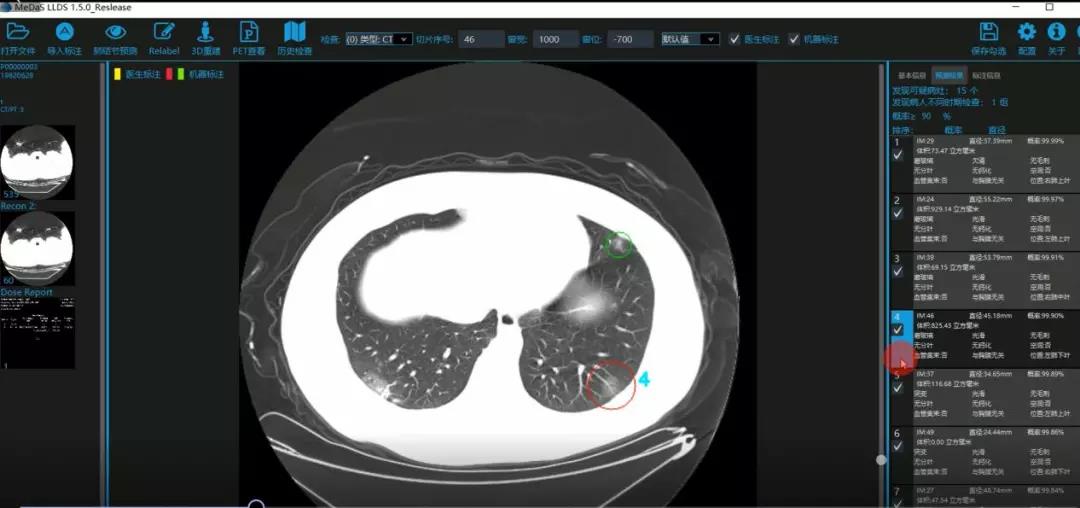

医护人员的好帮手:基于深度学习的新冠肺炎早期检测筛查系统

西电best365手机版官方网站智能软件与系统新技术研究所副教授张亮的爱人是西安交通大学第二附属医院抗疫一线的影像科医生,疫情发生以来,他们讨论最多的就是新型冠状病毒感染者的早期诊断问题。作为一名医护家属,身为高校科研工作者,张亮深知快速准确地诊断新冠肺炎早期患者对控制和防治疫情的重要性和挑战性。他与团队成员主动出击,通过远程网络会议,在前期医学影像处理的研究基础上加速科研攻关,反复讨论方案,屡次设计模型,与上海宽带技术及应用工程研究中心、上海交通大学医学院附属瑞金医院等合作单位的人员多次标注整理患者肺部CT影像数据到深夜。与此同时,他们依托上海瑞金医院、西安交通大学第二附属医院等的新冠肺炎疑似、确诊患者肺部CT影像,通过综合分析新冠肺炎患者的肺部CT影像特点(磨玻璃、体积大小、位置等特征),张亮团队加快技术攻关,设计开发了基于深度学习的新型冠状病毒的早期检测筛查模型系统。

对应新冠肺炎CT病灶检测效果

令人欣喜的是,通过对实际门诊数据排查测试,该模型可以减轻医护人员近80%的工作量,新冠肺炎患者的检测召回率超过95%。目前,模型系统正在进行最后的调试工作,很快投入到“战疫”一线,缓解医护人员紧缺、确诊检测工作耗时较长等问题,减少医护人员的工作时间和劳动强度,提高工作效率。